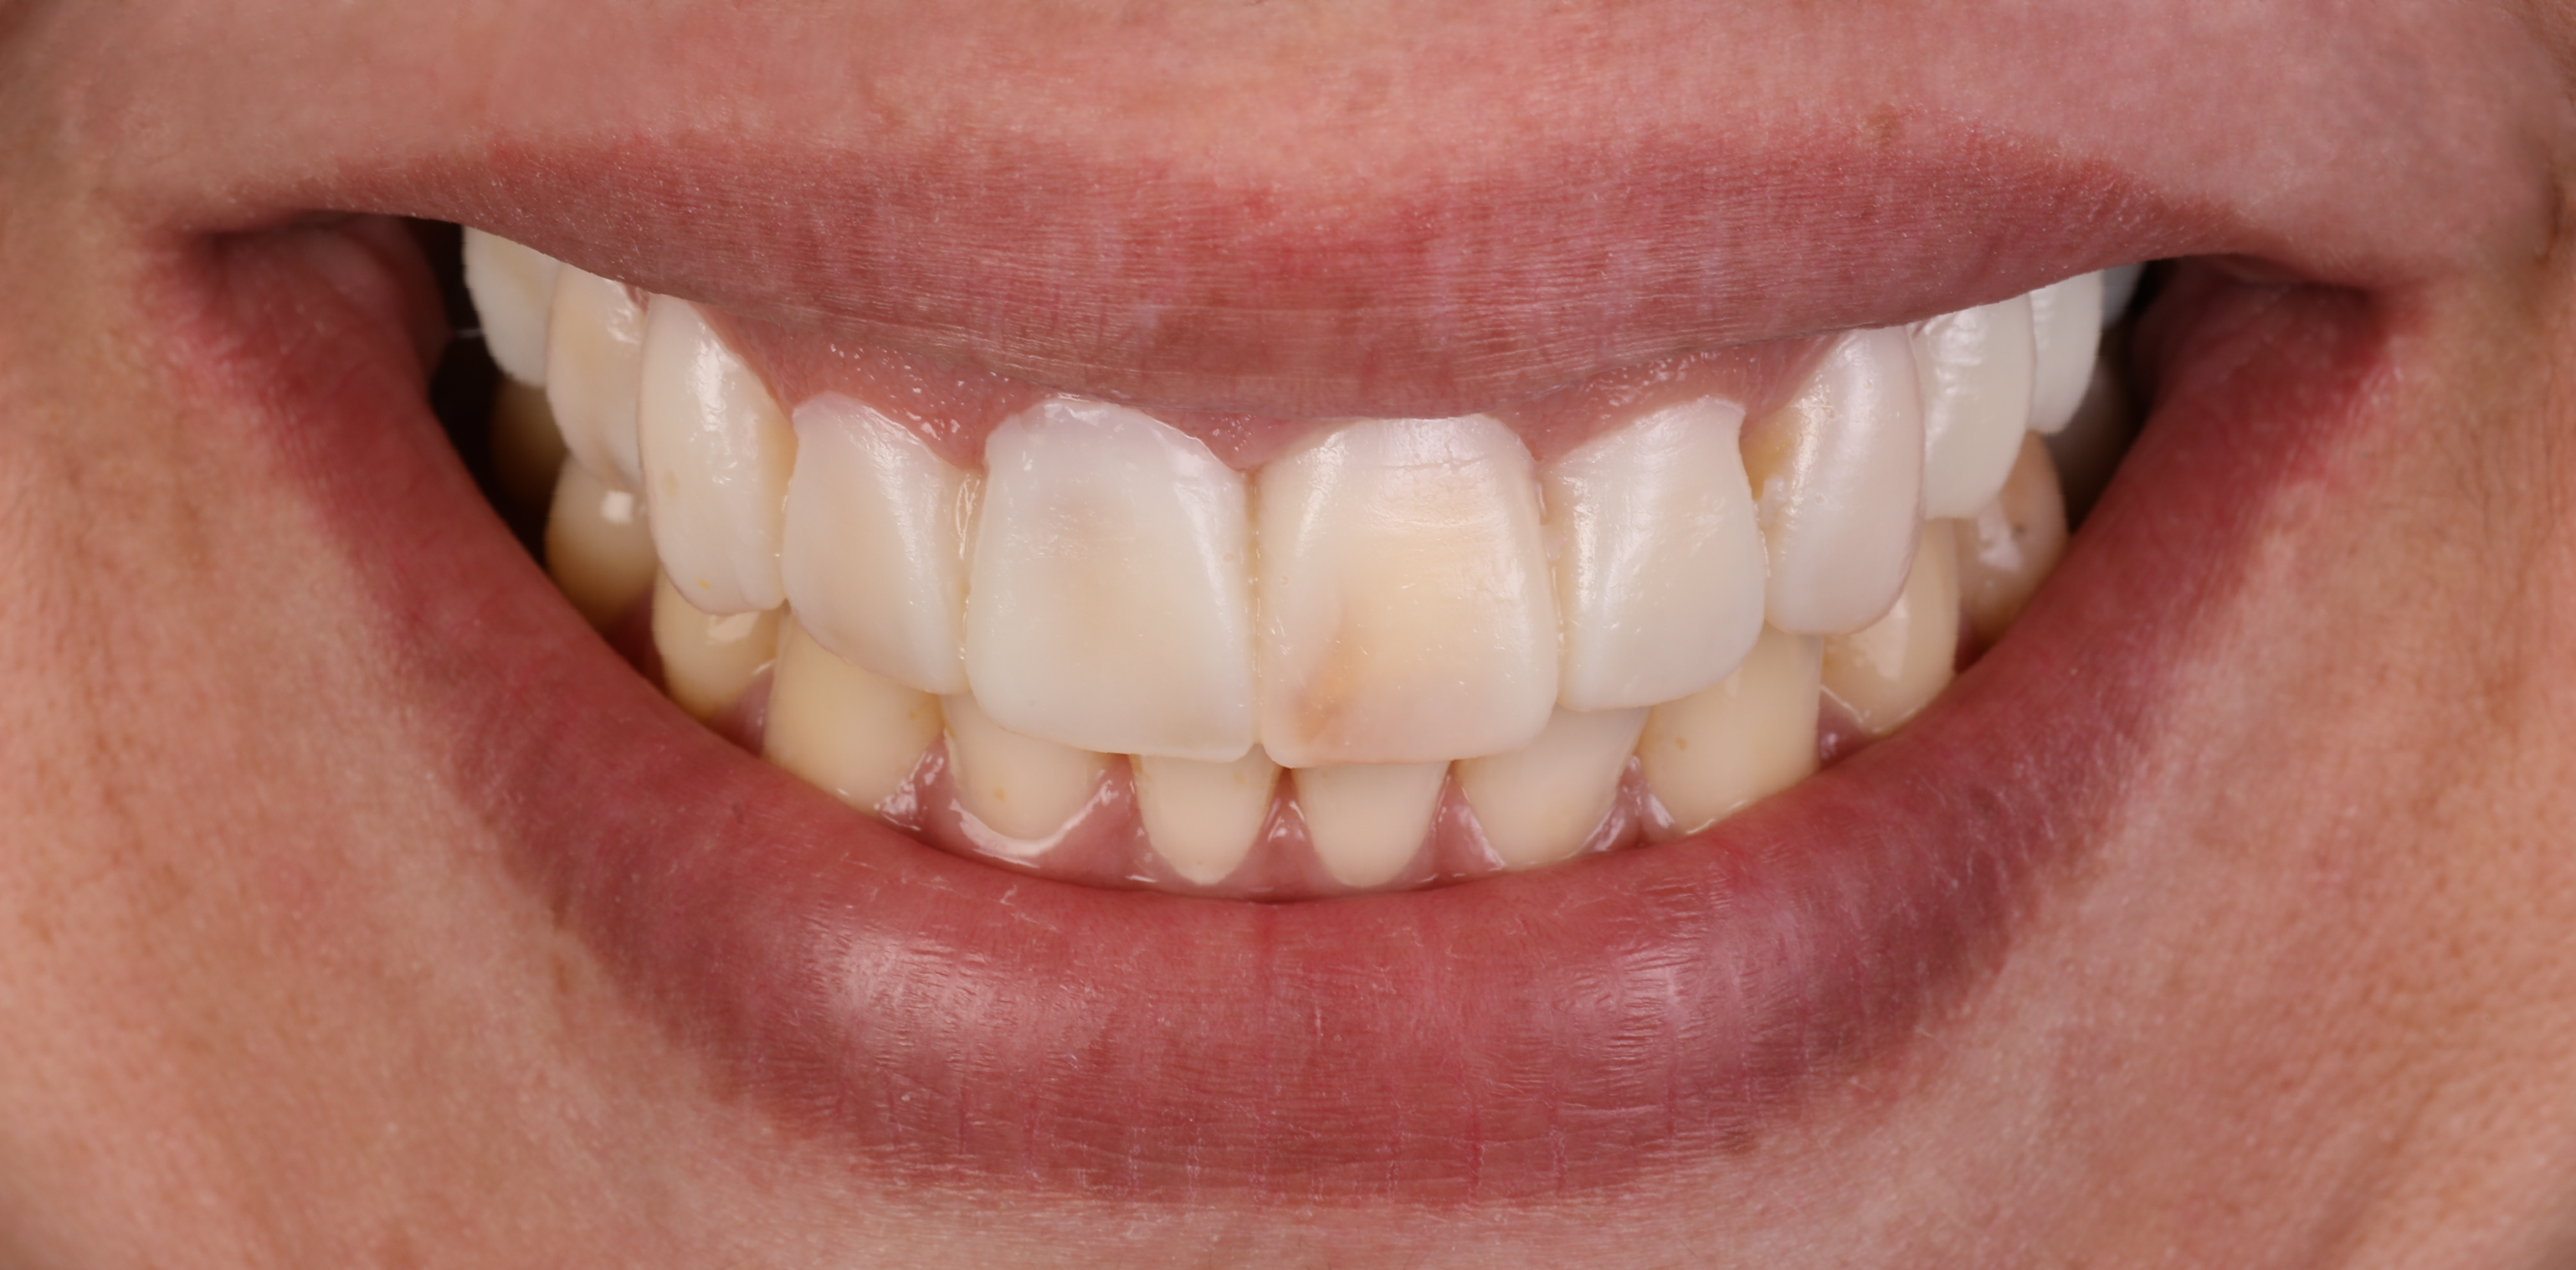

No final do tratamento de ortodontia, o que obtivemos foi um sorriso mais uniforme, que nos permitia direcionar agora a nossa atenção exclusivamente para a reabilitação oral.

Sorriso da paciente pós tratamento de ortodontia.